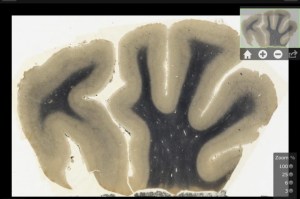

Un “genio parietale” – All’epoca, i tempi non erano maturi per un’approfondita analisi del cervello di Einstein. Gli studi sul cervello umano erano ancora poco sviluppati, cosicché nonostante le indagini minuziose compiute da numerosi scienziati non sembrò che la materia grigia di Einstein possedesse qualcosa di atipico. Fu solo nel 1985, in un articolo su Experimental Neurology, che si cominciò a parlare di una vera peculiarità del cervello di Einstein: il suo lobo parietale. E solo nel 1999, quando un’analoga conclusione fu raggiunta da una ricerca pubblicata sul prestigioso The Lancet, la notizia ottenne la dovuta visibilità. Confrontando il rapporto tra neuroni e cellule gliali del lobo parietale di Einstein con quello medio, si dimostrò che il fisico possedeva un numero superiore di cellule gliali rispetto alla norma, portando alla conclusione che ciò riflettesse un’inusuale incremento della capacità di elaborazione concettuale. La ricerca del 1999 dimostrò invece una dimensione fuori dal comune del lobo parietale inferiore: essendo l’area generalmente connessa a funzioni come l’orientamento spaziale, il pensiero matematico e il movimento, fu possibile giungere alla conclusione che questa singolarità anatomica del cervello di Einstein fosse alla base della sua straordinaria capacità di elaborare concetti astratti, come i suoi ben noti “esperimenti mentali” da cui emerse la teoria della relatività, e la sua capacità di ragionare non tanto sui numeri e le equazioni ma attraverso rappresentazioni mentali di tipo geometrico.

Un nuovo studio sulle foto –Dopo la morte di Harvey, nel 2007, i materiali di interesse scientifico in suo possesso, incluse le prime foto del cervello integro di Einstein, vennero trasferiti al National Museum of Health and Medicine dell’esercito USA nel Maryland. Ciò ne ha permesso un nuovo studio condotto da Dean Falk della Florida State University, che già nel 2009, sulla scorta di poche foto, aveva confermato le conclusioni sulla peculiarità del lobo parietale Einstein, insieme al neurologo Frederick Lepore della Robert Wood Johnson Medical School nel New Jersey e Adrianne Noe, direttore del museo dove sono state trasferite le foto di Harvey. Lo studio ha confrontato il cervello di Einstein con quello di altre 85 persone. Il peso,1230 grammi, risulta nella media, ma alcune regioni cerebrali presentano circonvoluzioni e pieghe in misura superiore alla norma, mentre la corteccia prefrontale – un’area collegata alla pianificazione e alla concentrazione – risulta analogamente piu’ grande del comune.

Un cervello incredibilmente complesso – “In tutti i lobi ci sono regioni che presentano circonvoluzioni eccezionalmente complicate”, spiega Falk sulla rivista Science. La domanda ora è se la peculiare conformazione del cervello di Einstein abbia permesso l’emergere delle straordinarie doti dello scienziato, o se l’estremo impegno nell’elucubrazione su temi ad elevata astrazione come quelli connessi alla fisica abbiamo stimolato una modifica della struttura cerebrale di Einstein. Gli esperti vogliono effettuare un confronto con il cervello di altri importanti fisici per verificare quest’ultima ipotesi. Anche l’enfasi posta dai genitori di Einstein sullo studio della musica, per la quale essi erano particolarmente portati, potrebbe aver stimolato lo sviluppo delle aree del cervello collegate alla creatività, come dimostra il fatto che nel precedente studio di Falk del 2009 una delle regioni del cervello di Einstein collegate al talento musicale risultava notevolmente sviluppata.